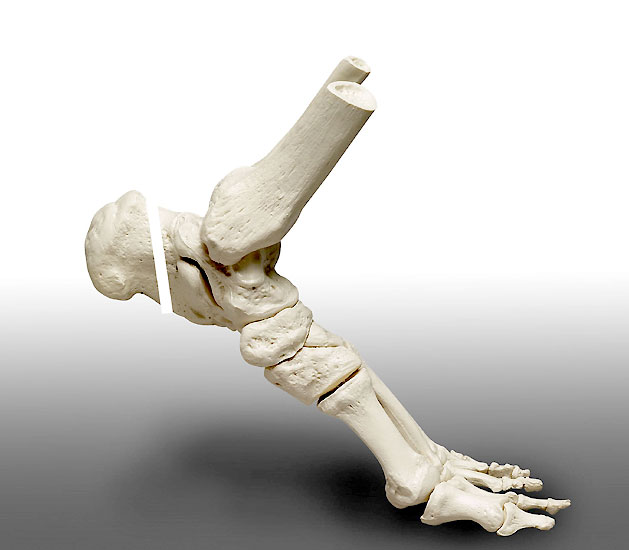

Abbildung 1

• Schwere, langstreckige degenerative Veränderungen der Achillessehne mit Ruptur (Abb. 1).